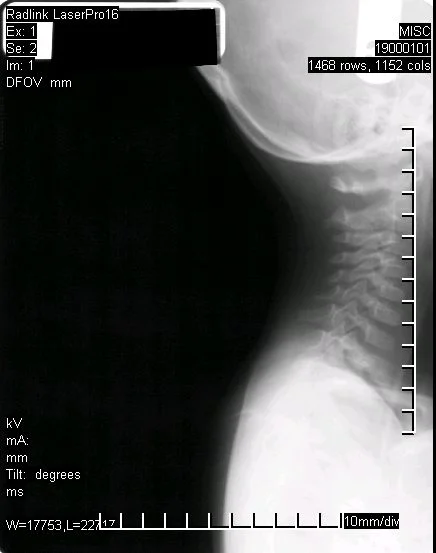

Before Corrective Care (manual short term adjusting)